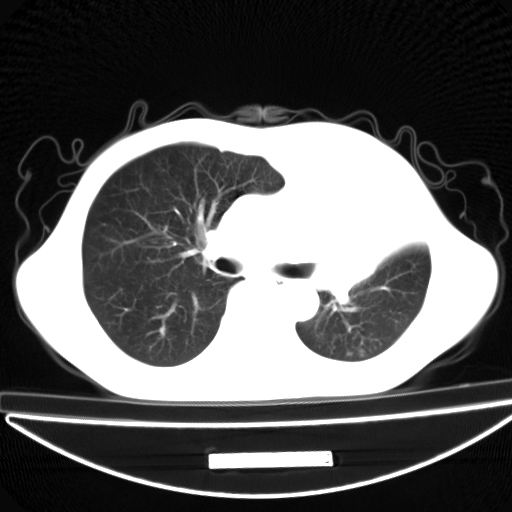

以下是引用杀毒软件在2009-4-28 17:58:00的发言:[br]考虑----左肺慢性肺脓肿形成继发上叶含气不良---抗炎后复查---待排肿瘤所致[br][br][本贴已被 杀毒软件 于 2009-4-28 18:01:26 修改过]